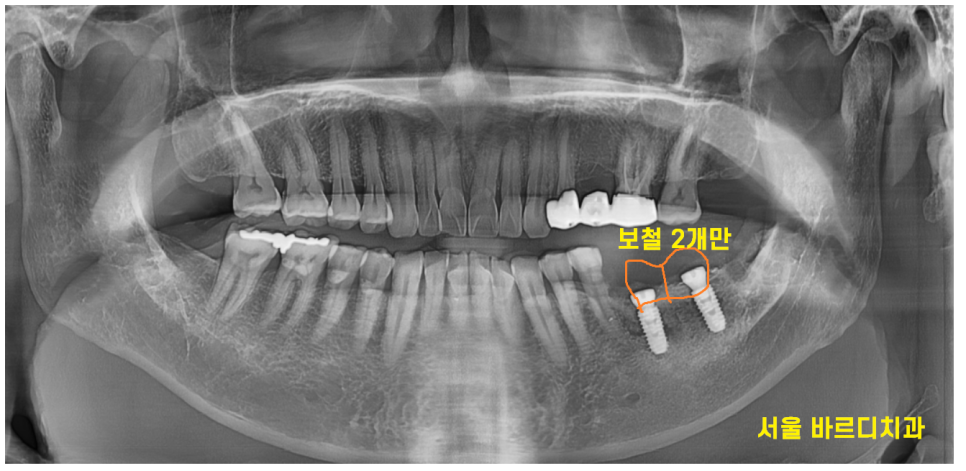

23.07.04

사진처럼 치아 개수대로

(임플란트 2개 보철 2개 )

치료하는 방안도 있었습니다.

위에 맞물리는 치아가 사랑니가 없었기에

2개 큰 어금니를 만들어 드리는 방법 역시

큰 문제가 되진 않았습니다.

오히려 환자분께는 보철 1개 가격을

덜어 드릴 수 있어서 경제적이라 말할 수 있죠!